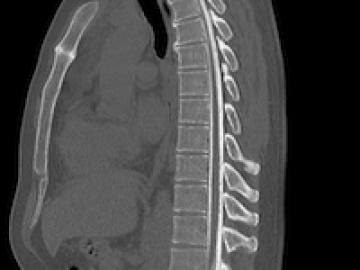

КТ  шеного отдела позвоночникаКТ грудного отдела позвоночникаКТ поясничного отдела позвоночника

• Грудной отдел позвоночника – самый длинный из всех. Он состоит из 12 позвонков, к которым крепятся ребра. КТ грудного отдела поможет обнаружить причины ухудшения осанки - кифоза, сколиоза, лордоза, межреберной невралгии, болей в области грудной клетки, связанных с защемлением нерва или патологией костей.